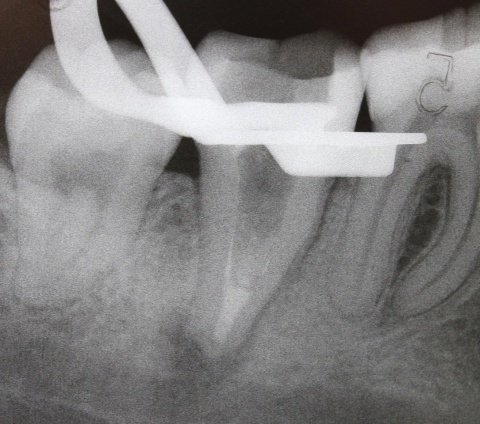

Im ersten Fall stellte sich die Patientin nach bereits erfolgter endodontischer Behandlung an Zahn 47 mit Beschwerden, die insbesondere bei okklusaler Belastung auftraten, vor. Die Provokation mittels Perkussion fiel positiv aus. Das daraufhin angefertigte Röntgenbild (Abb. 1) zeigte eine bis zum Apex reichende Wurzelfüllung mit apikaler Aufhellung und Ausdehnung der Osteolyse bis zum Dach des Nervus alveolaris inferior. Insgesamt war die Wurzelfüllung als inhomogen zu bewerten. Nach Aufklärung über die Therapiealternativen entschied sich die Patientin für einen Revisionsversuch.

Ein nach Applikation des MTA angefertigtes Kontrollbild zeigt den suffizienten apikalen Verschluss der Konstriktion in einer Schichtstärke von etwa vier Millimeter (Abb. 2). Gleichzeitig wird in der Aufnahme die ausgedehnte Kanalstruktur des Zahnes 47 deutlich.